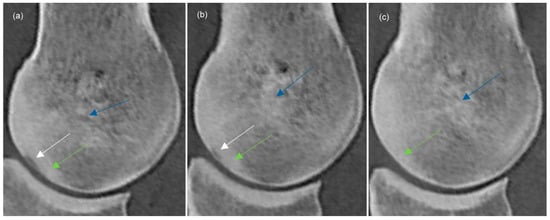

3.4. Subchondral Bone Thickening, Trabecular Bone Hyperattenuation

| Proximodistal extent (mm) | Median | 5.3 | 4.3 | 4.0 |

| 95% CI | 4.3–11.7 | 3.6–12.3 | 2.9–14.5 | |

| Dorsopalmar extent (mm) | Median | 2.1 | 1.7 | 2.1 |

| 95% CI | 0.7–1.9 | 0.5–1.6 | 0.5–2.5 | |

| Shape | ||||

| Proximodistally elongated | 12 | 6 | 5 | |

| Extending towards trabecular bone | 16 | 10 | 5 | |

| Depression | 1 | 1 | 1 | |

| Indentation | 2 | 1 | 1 | |

| Subtle | 2 | 4 | 2 | |